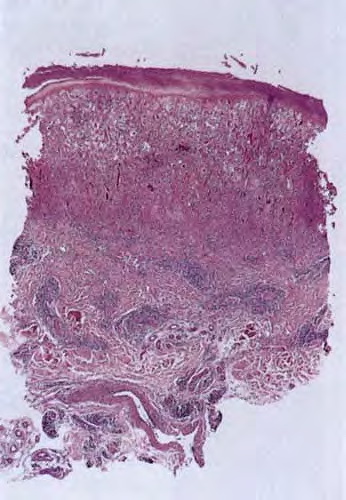

Atlas of skin histopathology

Herpes zoster = العقبول المنطقي = داء المنطقة